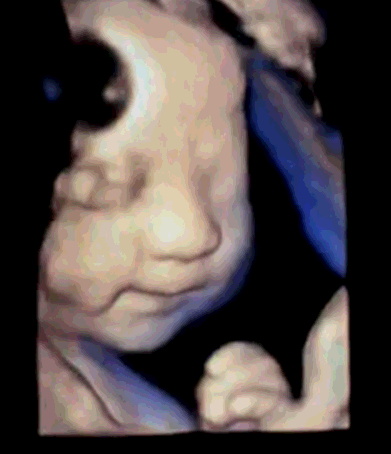

四维彩超的全称为四维彩色超声诊断仪,是目前世界上最先进的彩色超声设备。四维彩超的诊断资料有利于医生检测出各种异常,对于胎儿的成长发育做出准确的判断。那么四维彩超上的数据具体应该怎么看,美琳达妇儿医院四维彩超医生毕春英和您说一说关于四维彩超的那些事儿!

孕妇在孕期做四维彩超检查很有必要,它可以诊断胎儿是否会有患唇腭裂、无脑儿、脑积水、小头畸形、脊柱裂及脑脊膜膨出等症状;还有一些比较严重的情况,诸如:脐部肠膨出、内脏外翻、肾积水、多囊肾及巨膀胱、短肢畸形,联体畸形,唇裂、四心腔等。